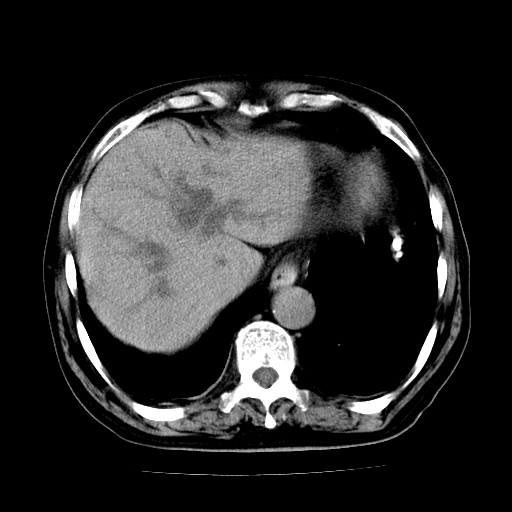

标题: CT25226:男,71岁,皮肤黄染四天。 [打印本页]

男,71岁,皮肤黄染四天。

肝内外胆管及胆总管上段扩张,考虑为梗阻所致,建议mrcp检查。

考虑胆总管癌并肝内外胆管扩张。

胰腺上端胆总管内见软组织影,强化不明显,结合临床,还是考虑低位梗阻性黄疸,胆总管癌可能性大